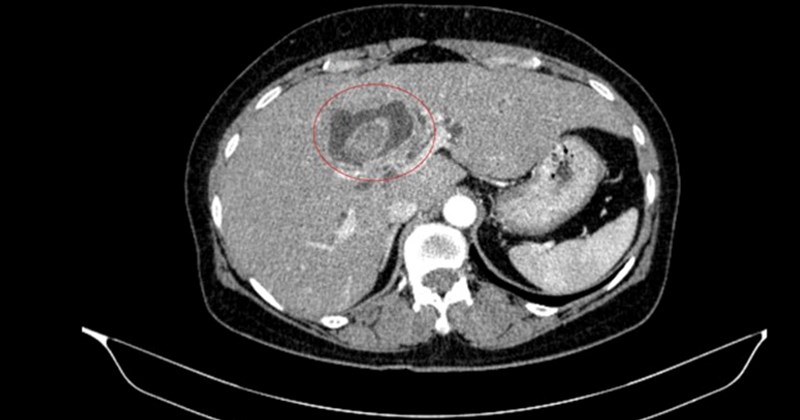

Bệnh nhân nữ, đến từ Hà Nội, đã đến khám tại Bệnh viện Bạch Mai sau khi xuất hiện các triệu chứng bất thường CafeF. Kết quả chẩn đoán cho thấy, bệnh nhân mắc hai loại ung thư khác nhau, một tình trạng được bệnh viện đánh giá là rất hiếm gặp CafeF. Hiện tại, thông tin chi tiết về loại ung thư và giai đoạn bệnh chưa được công bố cụ thể.